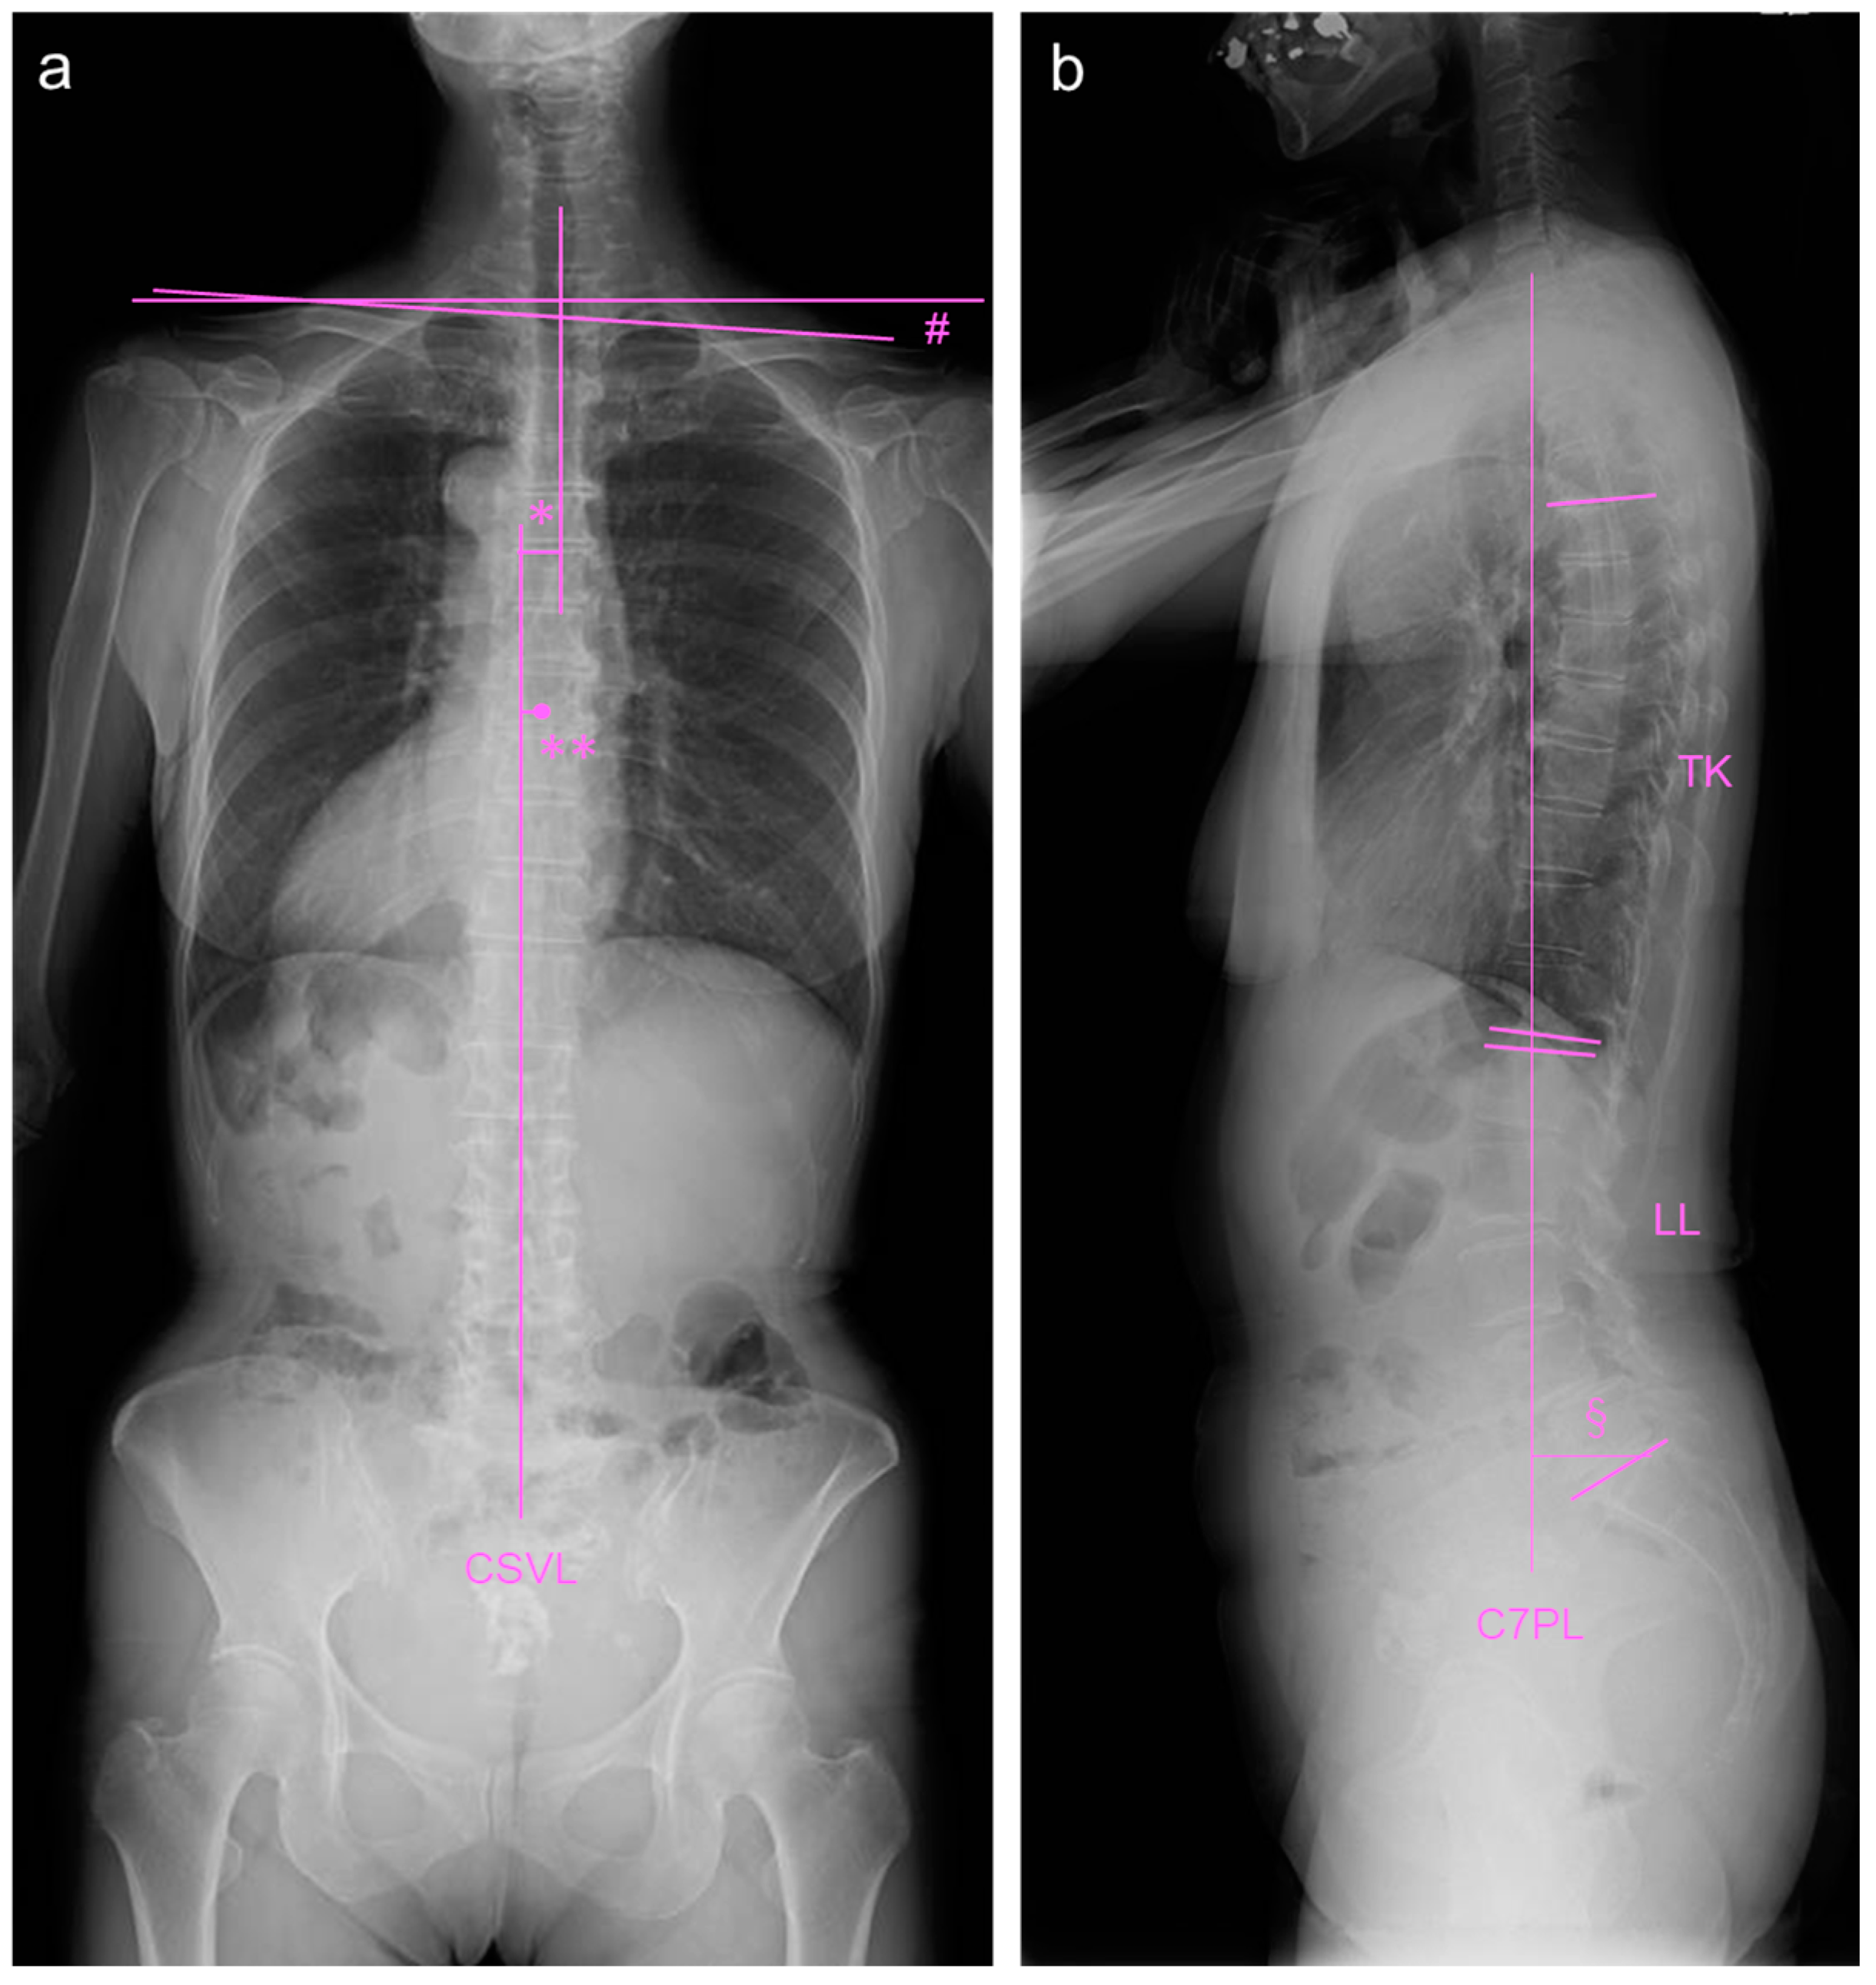

2.2. Image Examinations at First Visit

2.4. Image Examinations after Six Months of Daily Physical Exercise